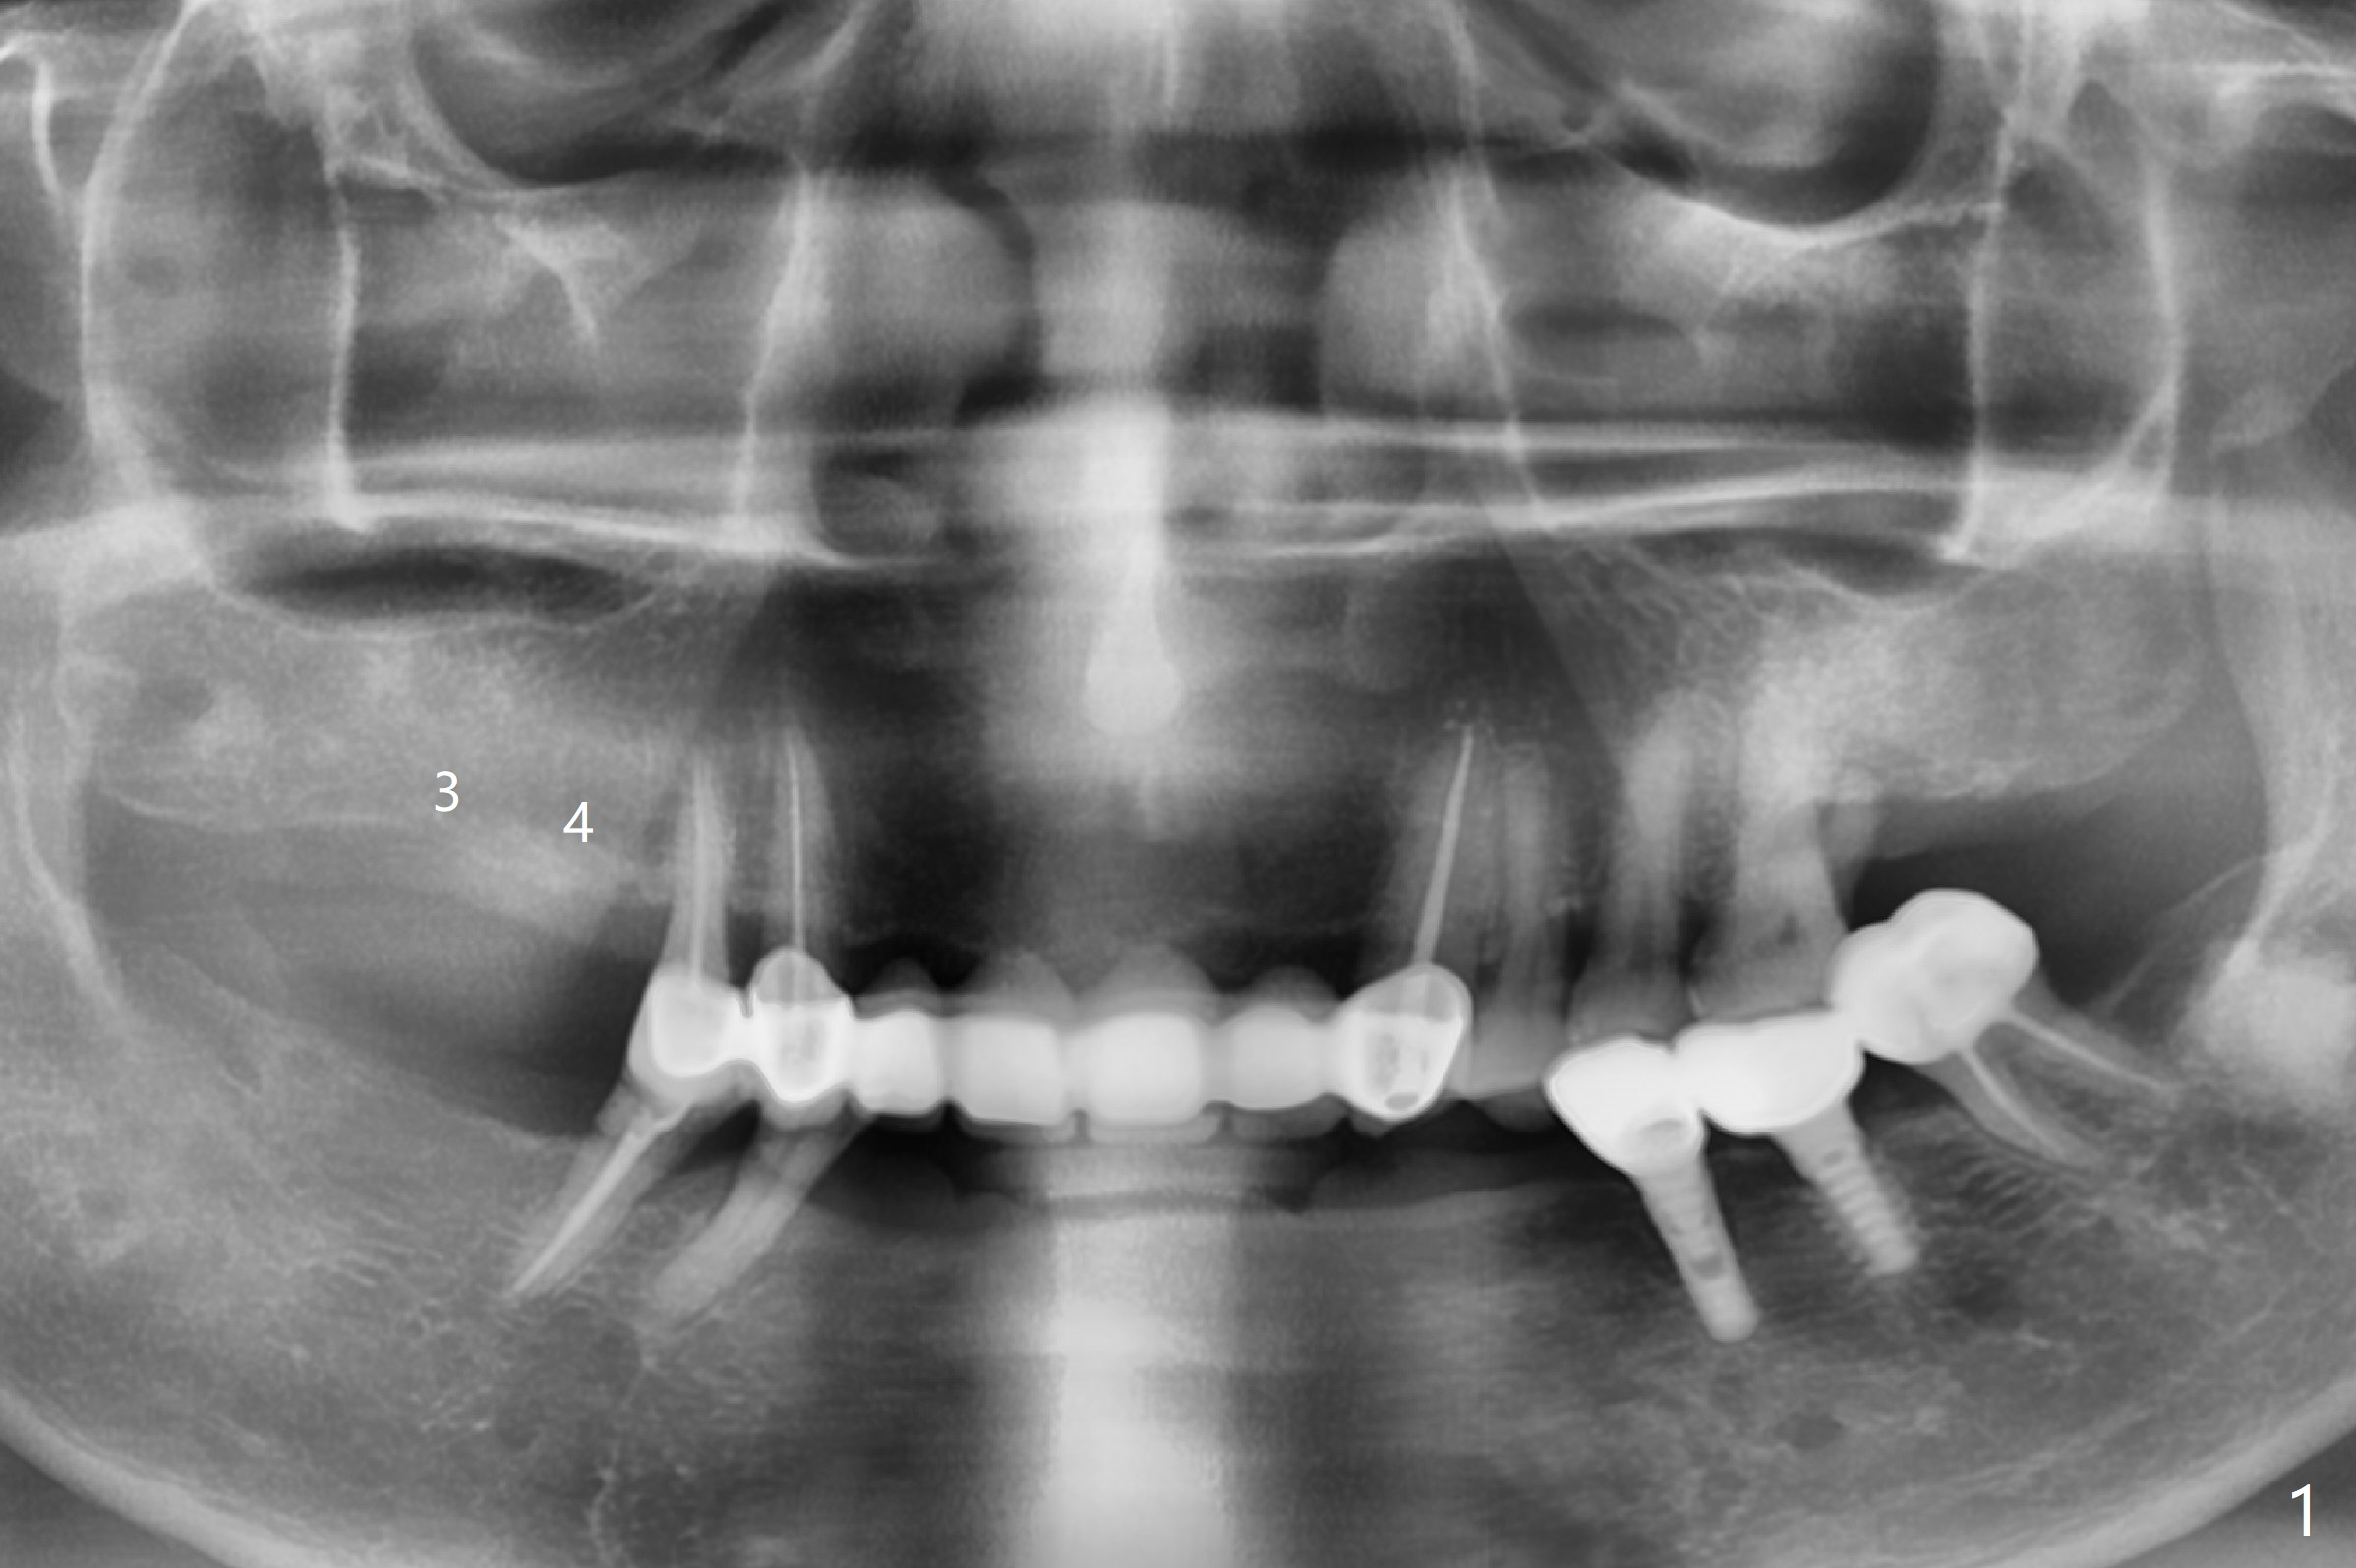

A 66-year-old woman requests implants at #3 and 4 (Fig.1). The main issue is loose bone with ~300 HU (Fig.2,3). Underprep must be a solution.